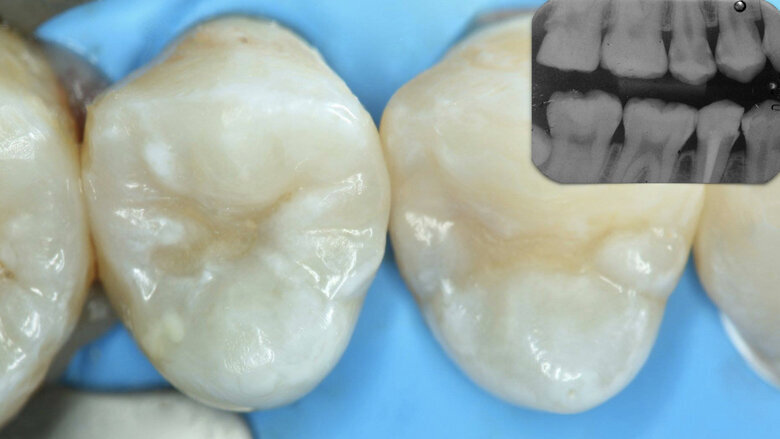

Figura 1. Lesiones de caries cavitadas en dentina activa (ICDAS 5) en dientes 11 y 21 en paciente másculino (Caso 1).

Paciente masculino de 65 años de edad se presenta al consultorio con lesiones de caries cavitadas en dentina activa (ICDAS 5) en dientes 11 y 21 (Figura 1). La lesión de la pieza 21 es extensa, mediante examen radiográfico y pruebas de vitalidad se diagnostica ausencia de compromiso pulpar. Como la lesión se extiende infra-gingivalmente, se opta por colocar dos hilos retractores 000 y 00 (Ultrapack, Ultradent, EE UU) y aislamiento absoluto con hilo dental tipo teflón y un clamp para anteriores (Figuras 2 y 3). Se inicia el procedimiento de remoción químico-mecánica utilizando un agente enzimático (Brix3000, Brix Medical Science, Argentina) durante 2 minutos (Figura 4). Utilizando curetas (Maillefer, EE UU) se elimina la dentina infectada (Figura 5) y el esmalte sin soporte dentinario (Figura 6) es eliminado con una fresa multilaminada (Figura 7) para mejorar el mimetismo y la adhesión al esmalte. Se complementa la instrumentación mecánica en el límite amelo-dentinario (Figuras 8 y 9).

Paciente femenino de 17 años se presenta en la consulta con sintomatología dolorosa tras estímulos térmicos. Clínicamente no se evidencia lesión, por lo que se indica una radiografía bite-wing y se observan lesiones de caries en piezas 24 y 25 (Figura 19) interproximales. Se coloca anestesia tópica y se procede con mínima apertura del esmalte con una fresa redonda (Figura 20). A través de esa cavidad se coloca el agente enzimático (Brix3000, Brix Medical Science, Argentina) para la remoción químico-mecánica (Figuras 21, 22 y 23). Tras limpiar la cavidad distal de la 24 a través de la cavidad de la 25 (Figura 24) se coloca una cuña y matriz (Figuras 25 y 26) para restaurar (Figura 27) con ionómero de vidrio encapsulado (EQUIA, GC Corporation, Japón).